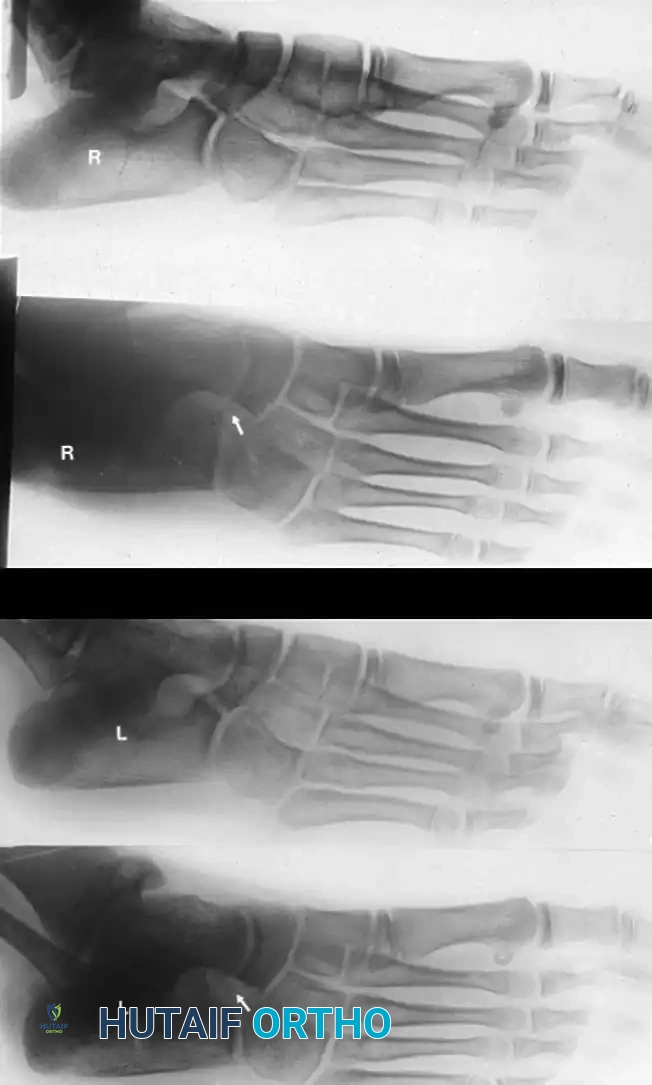

Radiographic Imaging

The 45-degree lateral oblique radiograph is the gold standard for diagnosing a calcaneonavicular coalition. The abnormal bar extends from the anterior process of the calcaneus (just lateral to the anterior facet) dorsally and medially to the lateral/dorsolateral extra-articular surface of the navicular. It typically measures 1 to 2 cm in length and 1 to 1.2 cm in width.

In incomplete coalitions, the adjacent bony margins appear irregular, sclerotic, and indistinct. The talar head may also appear small and underdeveloped.

While standard anteroposterior and lateral radiographs may show secondary signs (such as the "anteater nose" sign for calcaneonavicular coalitions or the "C-sign" and talar beaking for talocalcaneal coalitions), advanced imaging is often utilized in modern practice.

Advanced Imaging and Anatomical Reference Gallery

The following images illustrate various presentations, surgical exposures, and advanced imaging modalities (including CT and MRI correlates) utilized in the comprehensive evaluation and treatment of rigid pes planus and tarsal coalitions: